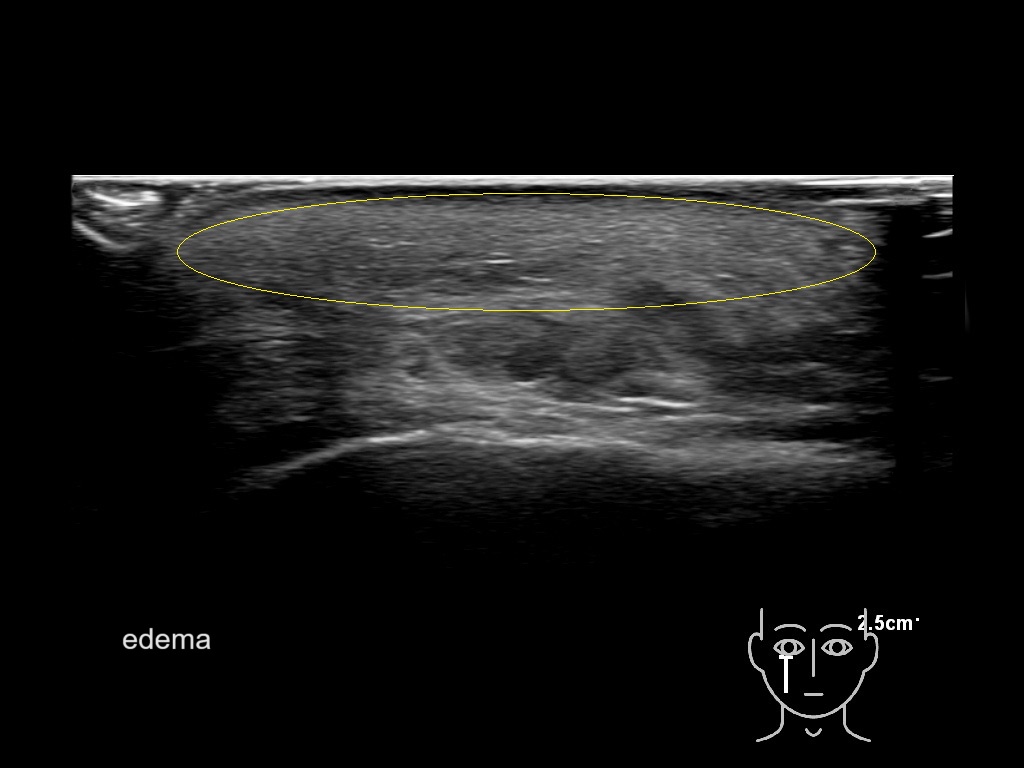

With ultrasound signs of inflammation can be visualized. Edema can be seen as a hyperechoic appearance of the subcutaneous fat, sometimes separated by hypoechoic fluid filled area’s, known as cobblestone appearance. Increased vascularization (hypervascularity) can be seen on colour Doppler. An abscess will appear as a fluid collection appearing as an irregular hypoechoic area with heterogeneous internal echoes and a thickened wall. Posterior acoustic enhancement can be present, and there is vascularity around but not within the mass. Under ultrasound guidance, abscesses can be managed by needle aspirations (18G) under antibiotic cover.

Study the first image to recognize the different layers. If you are sure about the layers, swipe to the second image to view the answer (if applicable).